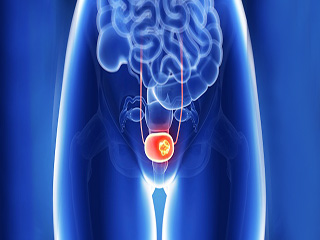

कैंसर, शरीर में कहीं भी असामान्य कोशिकाओं की अनियंत्रित वृद्धि है। स्तन कैंसर, त्वचा कैंसर, फेफड़ों का कैंसर, पेट का कैंसर, प्रोस्टेट कैंसर और लिंफोमा सहित 100 से अधिक प्रकार के कैंसर हैं। लक्षण प्रकार के आधार पर भिन्न होते हैं। इन असामान्य कोशिकाओं को कैंसर कोशिका, मैलिग्नैंट ट्यूमर या ट्यूमर कोशिकाएं कहा जाता है। ये कोशिकाएं शरीर के सामान्य ऊतकों में घुसपैठ कर सकती हैं। कई कैंसर और असामान्य कोशिकाएं जो कैंसर के ऊतकों (Tissues) की रचना करती हैं, उन्हें उस ऊतक के नाम से पहचाना जाता है, जो असामान्य कोशिकाओं से उत्पन्न हुआ है (उदाहरण के लिए, स्तन कैंसर, फेफड़े का कैंसर, कोलोरेक्टल कैंसर)। कैंसर उपचार में कीमोथेरेपी, विकिरण (Radiation) और सर्जरी शामिल हैं।

• प्रोस्टेट कैंसर (12.8 लाख मामले)